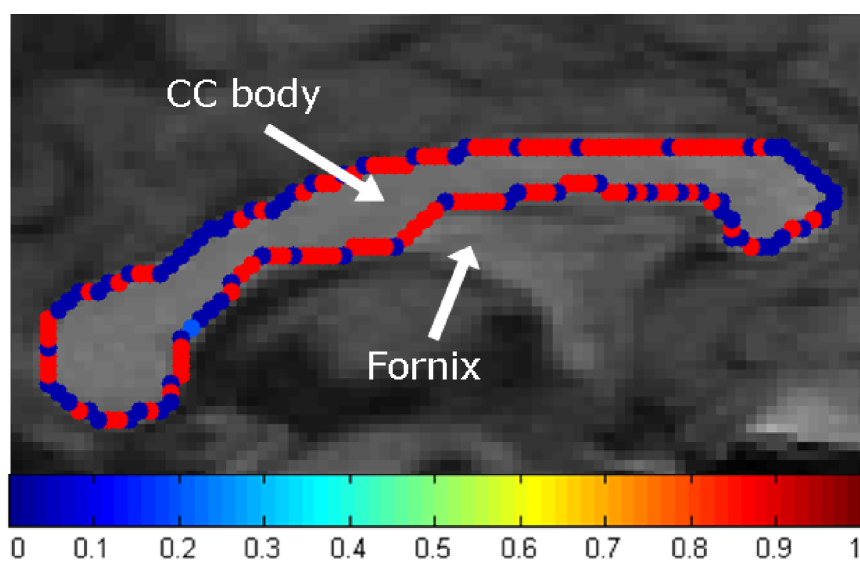

We also tested our method on clinical MR images of the corpus callosum (CC), which exhibits the known problem of a weak boundary where the CC meets the fornix (Fig. 3). Note how the contour obtained using globally optimal weights exhibits an optimal, yet undesirable, bimodal behavior (either blue or red in Fig. 3) completely favoring only one of the terms at a time. In comparison, our method automatically boosts up the regularization (stronger red in Fig. 3) at the CC-fornix boundary producing a better delineation. The segmentation results of all three methods for the same image are shown in Fig. 4.